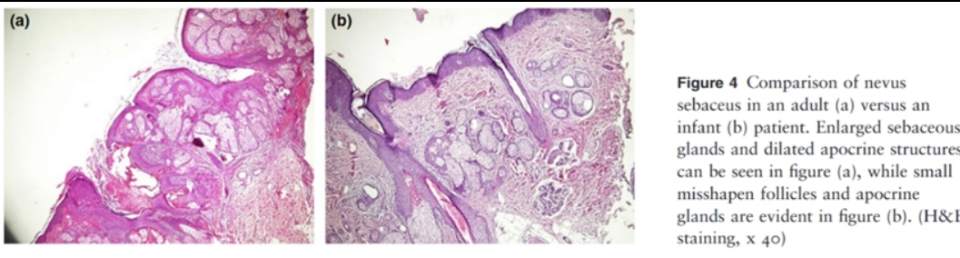

三、病理特点

皮脂腺痣的病理表现为表皮成分增厚及皮脂腺增生,表皮成分增厚包括角化过度、棘层增厚、乳头瘤增生,并且病变组织中观察不到长头发的成熟毛囊。疣状痣在皮肤镜下是可以看到毛发的,可以看到明显的棕色圆圈,病理表现只有表皮成分的增厚,没有皮肤附件成分异常。儿童期疣状痣的皮脂腺增生不明显,与疣状痣的鉴别需格外注意。